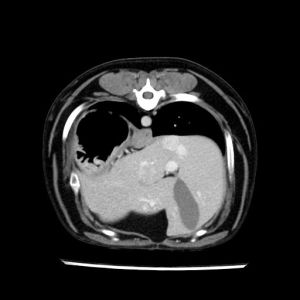

La lesione focale epatica , la ceus,la Tac e il chirurgo .